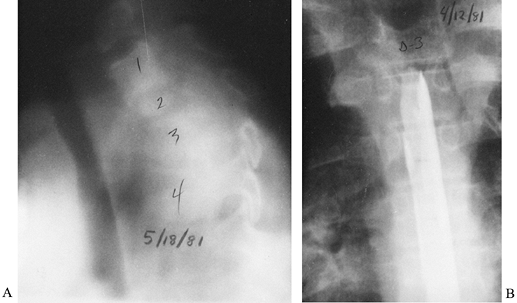

general anesthesia (Fig. 150.7).

Figure 150.7.

A radiograph demonstrates a Craig needle in the L4-5 disc space. Usually, a needle of this size can be used percutaneously in the lumbar spine. In the cervical spine, open techniques are safer. In the thoracic spine, a CT-guided needle biopsy or an open procedure is safer. |